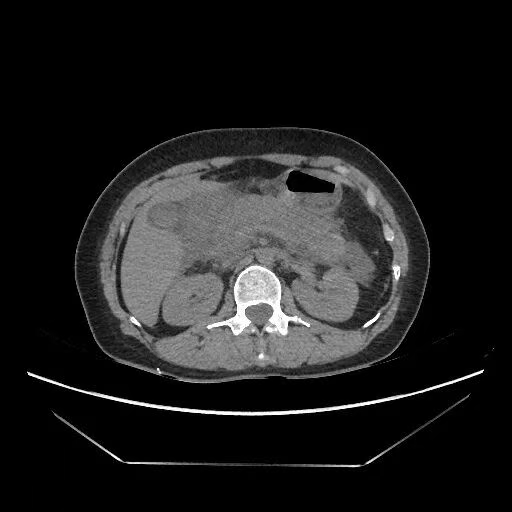

Acute pancreatitis is a disease primarily characterized by chemical inflammation due to the activation of pancreatic digestive enzymes within the pancreas, leading to self-digestion of the organ. Acute severe pancreatitis is often accompanied by organ dysfunction or local complications such as necrosis, abscess, or pseudocyst formation. If organ dysfunction persists despite medical treatment within 72 hours of onset, it may be considered fulminant pancreatitis, which has a high mortality rate.

Case 1: Xie, male, 40 years old, height 170 cm, weight 80 kg. Admitted to the emergency department with abdominal pain for 7 hours after alcohol consumption and intake of greasy food. After completing relevant tests and examinations, the current diagnosis is "Hyperlipidemic Acute Pancreatitis". The patient's condition improved after 3 days of comprehensive treatment in the Intensive Care Unit (ICU) and was then transferred to the Gastroenterology Department for continued treatment.

Case 2: Yao, male, 32 years old, height 170 cm, weight 58 kg. This is the fourth episode of pancreatitis after alcohol consumption. After completing relevant tests and examinations, the patient was admitted with a diagnosis of "Alcoholic Acute Pancreatitis". After initial treatment, symptoms worsened, leading to transfer to the ICU. The patient's condition showed significant improvement after 2 days of comprehensive treatment in the ICU, and was subsequently transferred to the Gastroenterology Department for continued care.

Case 3: Tian, female, 37 years old, height 160 cm, weight 60 kg. Experienced abdominal pain after binge eating and drinking. Symptoms significantly worsened after 2 days of treatment at a local community clinic, accompanied by signs of shock such as cold limbs and lethargy. The patient presented to the emergency department of our hospital's Minimally Invasive Surgery Department. After completing relevant tests and examinations, the patient was diagnosed with "Acute Severe Pancreatitis, Distributive Shock". The patient was transferred to the ICU for comprehensive treatment. After 5 days, the patient's condition improved, and they were transferred back to the Minimally Invasive Surgery Department for continued treatment.